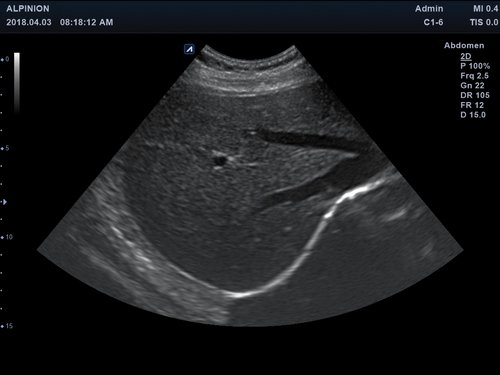

• Abdomen

Ein Konvex-Schallkopf oder ein Linear-Schallkopf wird per USB-Verbindung an das Alpinion minisono angeschlossen werden.

Frequenz 1 - 6 MHz 3 - 12 MHz

Scan-Tiefe 30 cm 10 cm

Sichtfeld 78 ° 38,4 mm